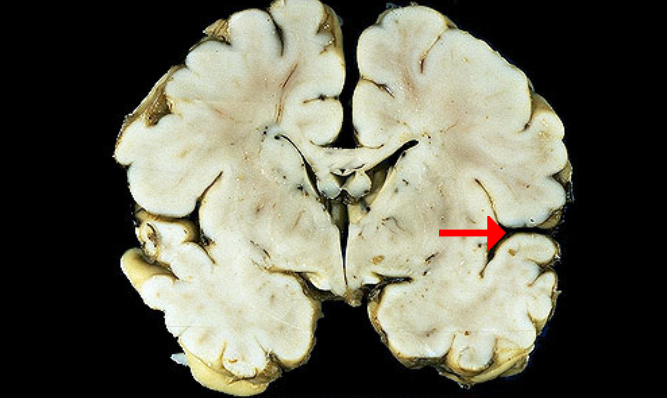

Label this brain structure

Cingulate gyrus

Label this brain structure

Substantia nigra

Label this brain structure

Optic tract

Name this brain structure

Hippocampus

Label this brain structure

Cerebral aqueduct